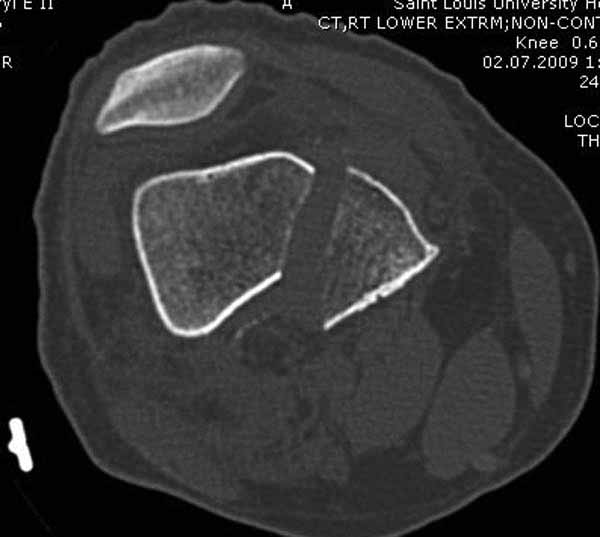

>Сразу не обратил ваше внимание именно на это, что сломаны оба мыщелка, и больший является именно медиальным мыщелком

А теперь по поводу лечения перелома. Среди всех чрез/меж-мыщелковых переломов в 38% сопровождются переломом в корональной плоскости, т.е перелом Hoffa. Nork et al, J Orthop Trauma, 87:564, 2005.

По снимку вроде одиночный простой мыщелковый перелом, и такой внутрисуставной перелом не обязательно дистрагировать на скелетном вытяжении, потому что не не нарушается непрерывность колонны с одной стороны. И для таких простых переломов подойдет любой метод: 95 градусная пластина, Lat. Condylar Butress пластина или ретроградный гвоздь. А для особых энтузиастов которые желают антеградную фиксацию, возможно легко найти трохантер у алкоголиков или дистрофиков. А вот у откормленных Макдональдскими гамбургерами? Если поискать у них тоже можно найти, но стоит ли?

У больных как в этом случае, с вовлечением двух мыщелков правильно, что сделали вытяжение до операции. Здесь имеется флексионный компонент на другой стороне, и я бы рекомендовал операцию делать из двух доступов. Сперва фиксировать медиальную колонну custom made пластиной, обычно 1/3 тубулярной пластиной в 4.5 мм, потому что пока производители опаздывают с медиальной пластиной.

Пластину надо устанавливать на апексе перелома, иначе фрагмент начнет сползать. А на второй стороне, если имеется большой одиночный фрагмент тогда проблем не бывает, и их можно собрать компрессирующими винтами. Проблема наступает тогда когда многофрагментраность на латеральной стороне, где надо применить комбинированный метод, иногда несколькими пластинами. Или сменой позиции установки пластины, чтобы максимально прикрыть перелом и создать боковую поддержку.